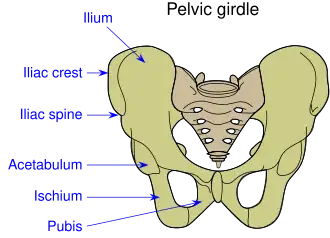

O acetábulo, ou cavidade cotiloideia (em latim: Acetabulum) é uma depressão na pelve, formando uma superfície côncava. A cabeça do fémur articula-se com a pelve no acetábulo, constituindo a articulação coxo-femural, vulgarmente conhecida como anca em Portugal, ou como quadril no Brasil.

O osso coxal é constituído por três porções ósseas, que se unem para constituir o acetábulo. O ísquio, que constitui cerca de dois quintos da estrutura, forma os bordos inferiores e laterais do acetábulo. O ílio forma o bordo superior, sendo o constituinte de cerca de dois quintos da estrutura do acetábulo. A porção restante é constituída pela púbis, mais perto da linha média. Os três ossos encontram-se unidos pela cartilagem trirradiada (uma faixa em forma de Y), que se ossifica, formando o fundo do acetábulo.